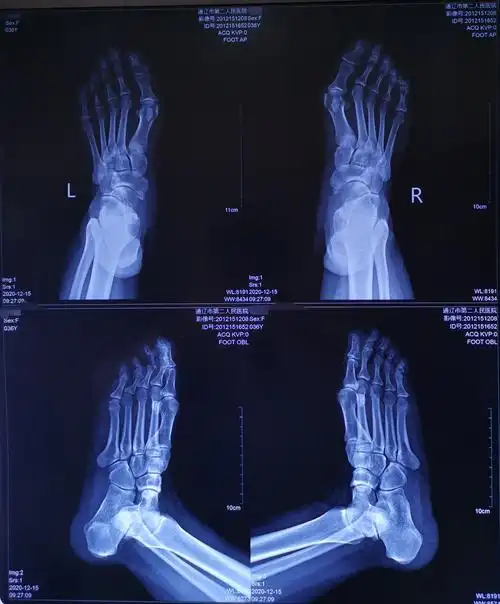

陈圣英分析拇外翻矫正削骨不是关键矫正才是关键